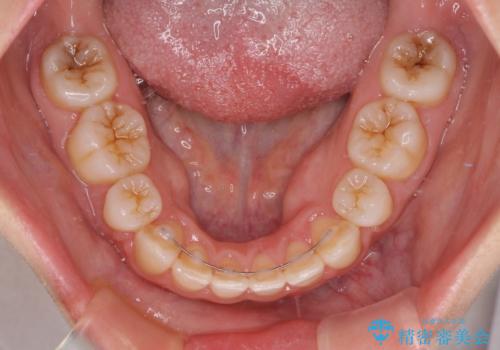

口元の突出感が改善されると睡眠中の口呼吸が予防でき、鼻炎などの疾患予防に繋がると言われています。

- 矯正治療後の保定が不十分だと後戻り(元の位置に戻ろうとする動き)をします